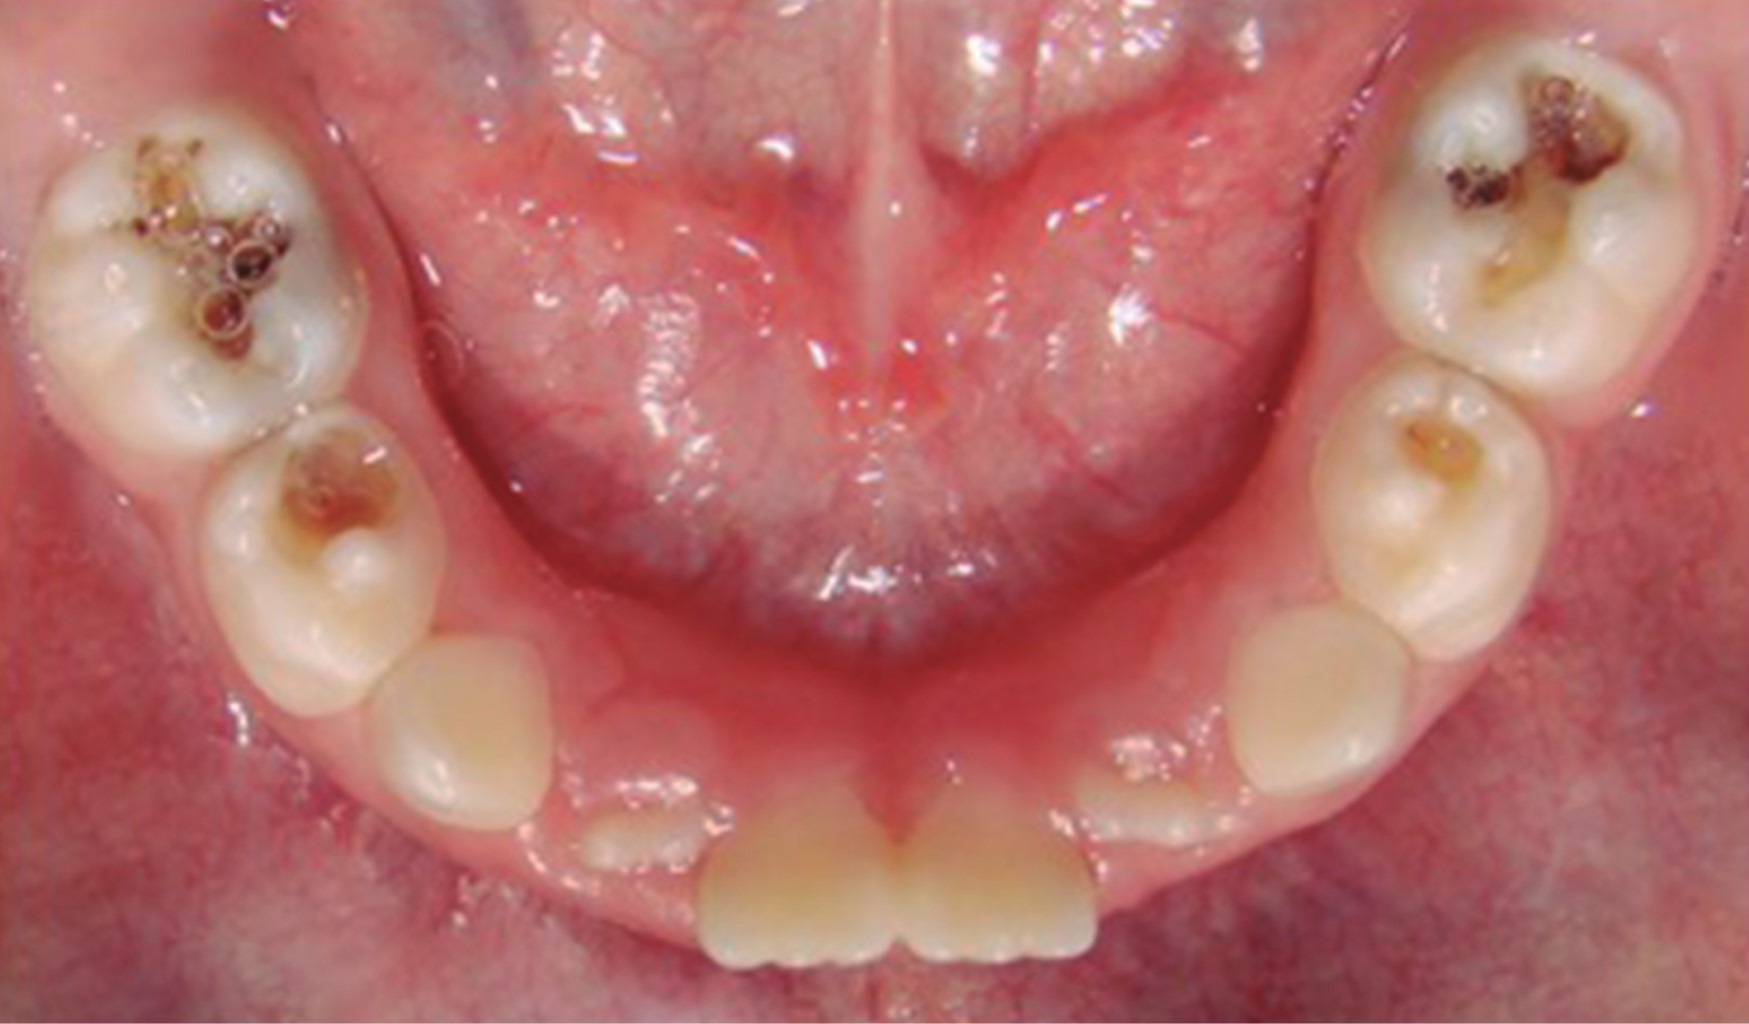

Figure 2